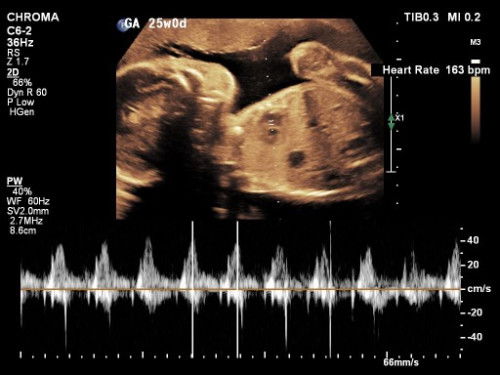

saya pas pertama kali ikut yoga hamil usia hamil 21 weeks, pertama kali dicek bidannya pakai doppler juga susah nyari djj nya bun. agak lama baru terdengar samar. padahal lagi nendang2 adeknya. karena lemak perut ketebelan 🤣🤲🏻 tapi tiap cek ke obgyn alhamdulillah jelas banget djj nya bun. bisa dicek juga berapa bpm nya kayak gini. jadi jangan terlalu overthinking ya bunda. kalau penasaran bisa langsunh cek ke obgyn juga yaa.

aku sampai usia 20 week msh blm jelas kedengaran Bun periksa di bidan soalnya cuma pakai doppler kan dan memang perutnya lumayan tebal, mau yg kedengaran jelas usg aja ya Bun ke SpOG dari 10 week sdh ad kok djj nya